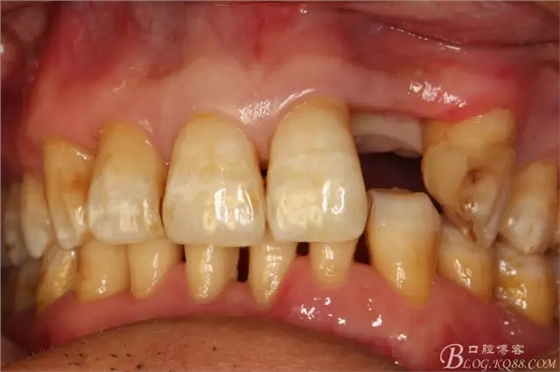

圖3.術(shù)前口內(nèi)照片:正面觀閉口位

圖4.左側(cè)側(cè)面觀,22間隙正常,23近中輕度扭轉(zhuǎn)